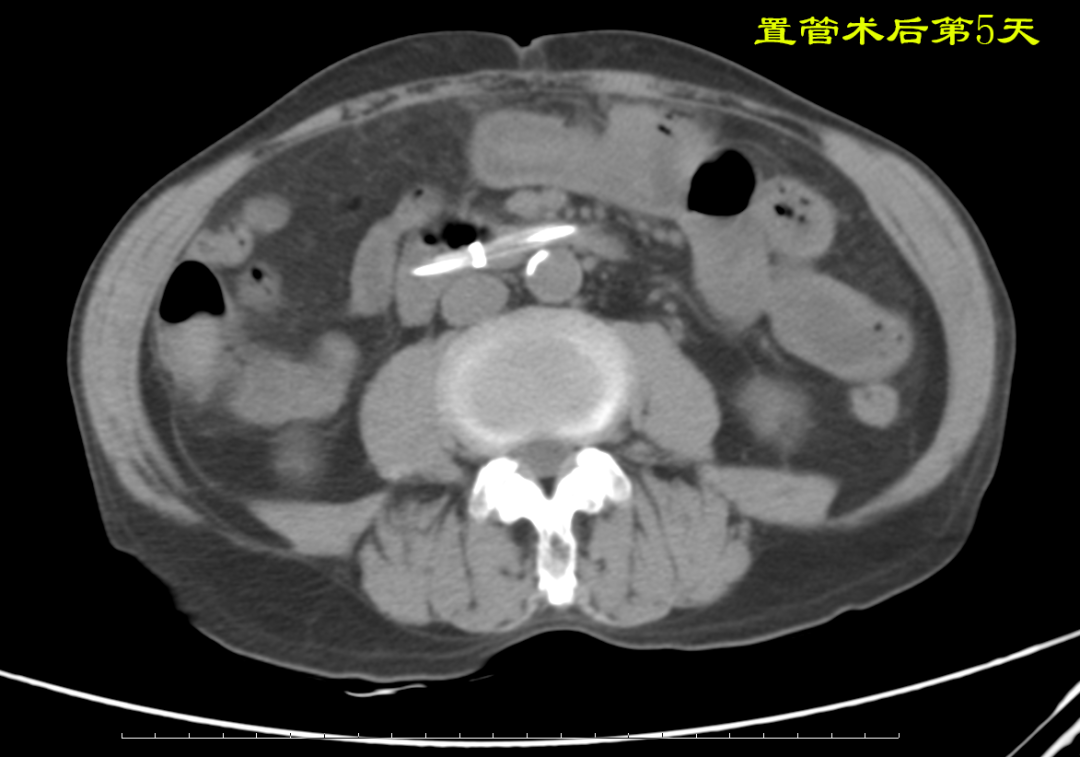

病例:患者男性,74岁,因“腹痛、腹胀伴呕吐、肛门停止排气排便20小时”于2021年7月24日入住我院普外科。患者1月前因回肠穿孔于我院普外科手术治疗,入院后明确诊断为术后粘连性小肠梗阻,经胃管引流等保守治疗无好转。因患者有严重心肺疾患,再次手术风险较大,并且术后再发粘连性肠梗阻的可能性也很大。经过与患者家属沟通后,最后决定采用胃镜引导下置入经鼻插入型肠梗阻导管技术来治疗肠梗阻。由我院消化内科副主任医师杨开余完成操作,耗时大约40分钟,患者术后第5天开始排气排便,腹痛、腹胀症状迅速消失,术后第7天拔除肠梗阻导管,恢复饮食。拔管至今已10天,患者已出院。随访患者无腹痛、腹胀,排便正常。

良好的引流是治疗肠梗阻的基本措施,低位小肠梗阻置入胃管引流常难以奏效,以往大多需要再次手术,而再次手术后粘连的几率高达70%。经鼻插入型肠梗阻导管就是将一根3米多长,内有四个腔道的管道置入十二指肠后,在重力和肠道蠕动的作用下,导管先端部将自动向前运动,直至到达梗阻部位。在导管到达梗阻部位后,可进行双对比造影检查了解狭窄病因,也可以对狭窄处进行扩张,还可以作为支架起到肠排列的治疗效果。肠梗阻导管治疗小肠梗阻属于微创型手术,具有痛苦小、疗效好、费用低、预防再次粘连等优点。